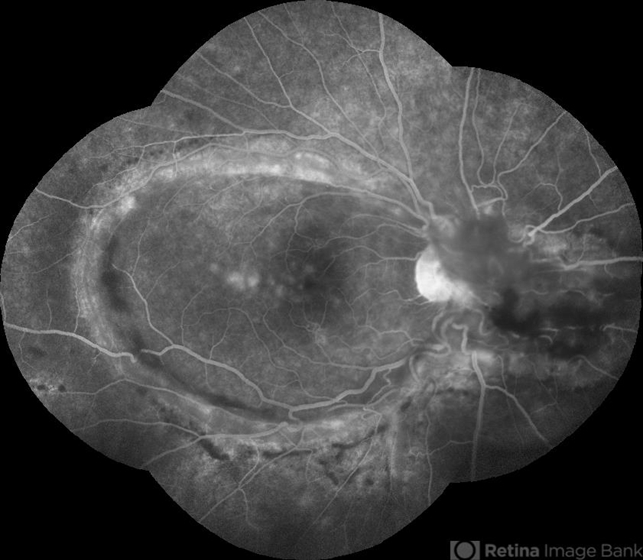

- Perimacular Fold in Tersons Syndrome

- Terson's Syndrome, macular fold, submacular hemorrhage, sub internal limiting membrane haemorrhage

- Fundus Fluorescein Angiography picture of a 36-year-old male with chronic liver disease who has undergone 25G vitrectomy for Vitreous and sub-ILM haemorrhage from Terson's syndrome.